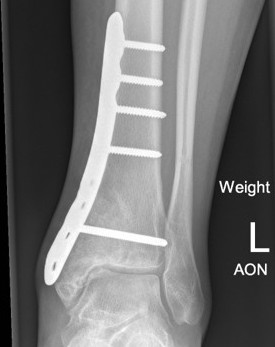

Weight bearing joints

Options

Currettage and bone graft

Currettage / bone graft / fixation